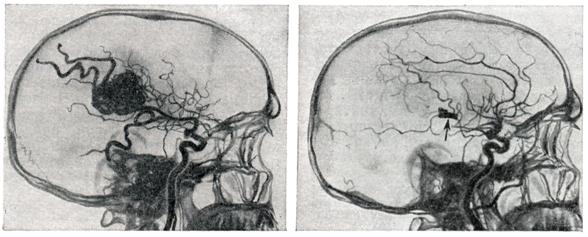

Рис. 4.

Ангиограмма больного после полного удаления большой артерио-венозной аневризмы теменной и задних отделов лобной доли (видны клипсы). Слева — ангиограмма больного до операции.

Радикальным методом лечения является полное иссечение артерио-венозной аневризмы (рис. 4). Однако при большой распространенности аневризм и их расположении в глубинных, жизненно важных структурах мозга такая операция может оказаться невыполнимой.